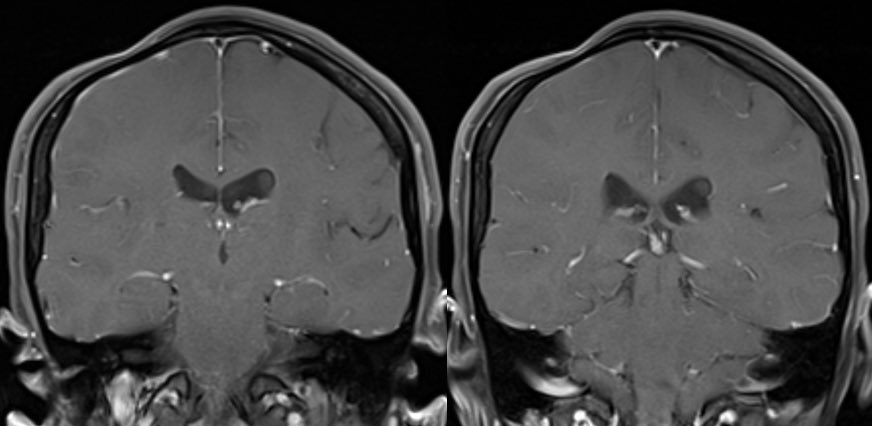

⭐️ Tips for distinguishing treatment change from tumor progression from my own experience and the literature ☢️

#Neurosurgery #Neurology #radres #futureradres @TheASNR @UMiamiHealth #MRI @Radiopaedia #ENT #Medicine @PennRadiologyImage

Image

🔷For glioblastoma we need to rely on many clinical and imaging features to distinguish (no one feature is specific enough to diagnose so we need to take the whole clinical and radiographic picture into account)

🔷Important features to consider:

▶️Recency of treatment

💡 Radiation necrosis is usually seen from 2 to 32 months after therapy, with 85% of cases occurring within 2 years. A new or worsening abnormality starting 3 years after completion of radiation therapy is very unlikely to be due to pure radiation necrosis. In the first 2–3 years, both tumor and radiation necrosis can occur

▶️Clinical symptoms (although both tumor progression and radiation necrosis can be symptomatic, we want to be careful calling tumor progression in a patient who is clinically doing well as this is devastating news for the patient and there are only limited options for therapy)